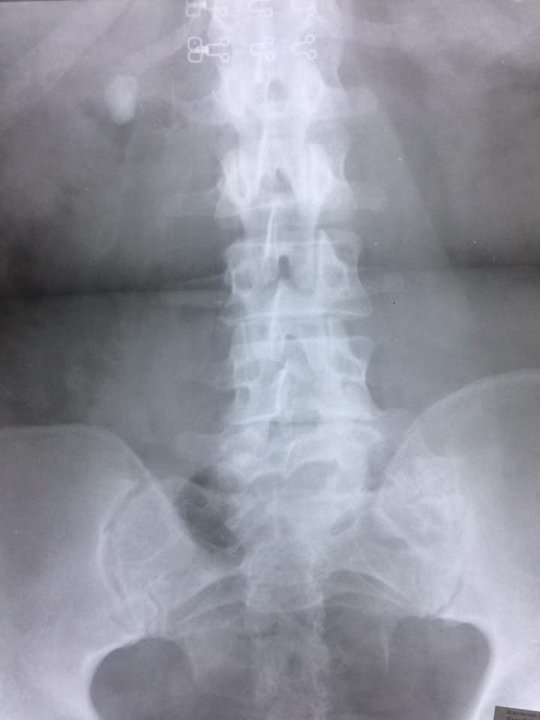

До центру ендоурології Ковельського МТМО звернулася жінка зі сечокам'яною хворобою: камінь миски правої нирки. Про це інформують на сторінці закладу.

Діагноз встановили близько 2-х років тому, проте методи консервативного лікування були неефективними.

Після проведення додаткових обстежень (УЗД та екскреторна урографія) лікарі-урологи провели перкутанну нефролітотрипсію справа. Операція тривала до 45 хвилин.

"Цей клінічний випадок був непростий через наявність супутньої патології у пацієнтки. Вражаючим також був розмір самого каменя 2,5х3,0 см. Проте нашим урологам Миколі Зубку та Мирославі Гаврилюк успішно вдалось видалити камінь повністю та з мінімально можливим травматизмом для пацієнтки. А лікар-анестезіолог Самарчук Т.В. зробила операцію безболісною та комфортною за допомогою епідуральної анестезії", - йдеться в дописі.